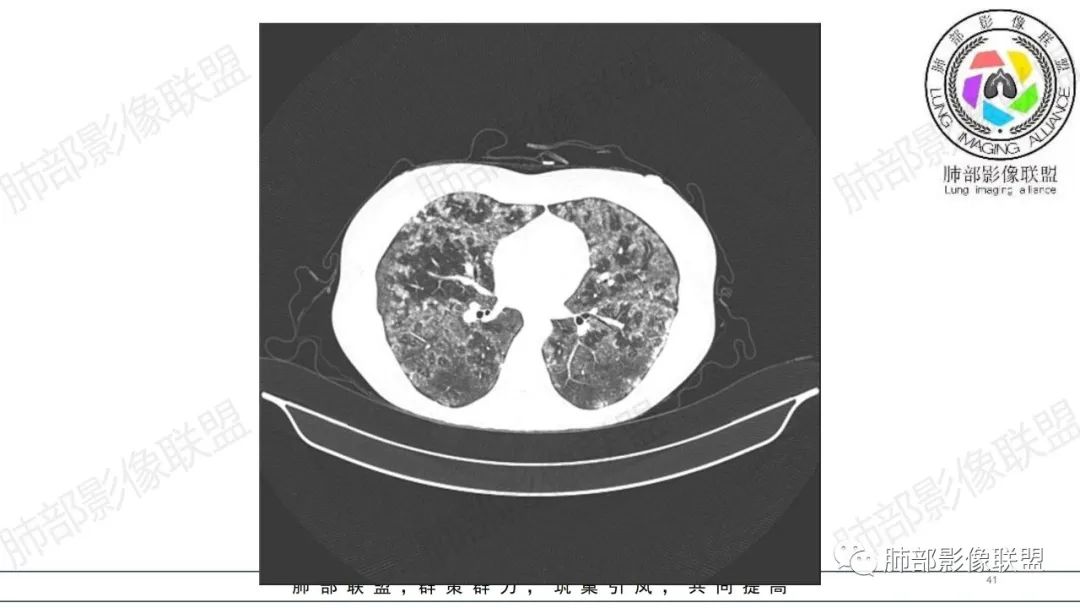

34岁女性患者,“哮喘”病史30年,近期有可疑刺激性气体吸入史;因乏力半年,咳嗽、憋气、发热4天就诊;6.1CT提示双肺广泛毛玻璃影及粟粒样结节,胸膜下闲置及血管周闲置,可见树丫征,部分小叶间隔增厚。考虑:1.过敏性肺泡炎,有可疑刺激气体接触史,胸膜下闲置,广泛毛玻璃影,地图样分布,粟粒结节边界模糊,支持过敏性肺泡炎,但糖皮激素治疗效果不佳,且动态复查血常规血红蛋白进行性降低,过敏性肺泡炎 不符合;2.肺含铁血黄素沉积症:患者30“哮喘”病史,可能为肺含铁症状,肺部CT提示双肺弥漫毛玻璃影及粟粒结节影,中下肺明显,肺底部分小叶间隔增厚,近期咳嗽、憋气、发热,血常规血红蛋白进行性下降,考虑肺含铁急性期症状,但临床无咯血症状,肺含铁不典型。综合考虑:肺含铁血黄素沉积症>过敏性肺泡炎。

年轻女性 ,急性喘息发热,肺部影像弥漫磨玻璃密度,部分细小腺泡结节,胸膜下黑线显示,短期复查,病变密度增高,下肺明显,血管周围肺组织累及较少、且逐渐成小叶间隔分布。考虑弥漫肺泡内病变,并经淋巴道转移,下肺比上肺明显,多为免疫细胞功能下肺较强。1.过敏性肺泡炎,有相关病史,三层密度特点、头尾测分布,符合。2 肺泡微石症,多有钙化,且缓慢起病,病程不太符合,放待排。3 吸入相关肺损伤,有病史,疾病演变过程也符合渗出-肉芽肿改变,建议详细询问病史。4 感染性病变,结核?病变气道分布为主,如此弥漫且没有树丫不符合。5.巨细胞病毒,可以磨玻璃 结节 改变,没有免疫缺陷病史。最后考虑吸入所致 1过敏性肺泡炎、吸入性肺损伤 鉴别肺泡微石症。

肺内气腔磨玻璃结节,肝脾肿大,治疗后间质改变,弥漫大B可能